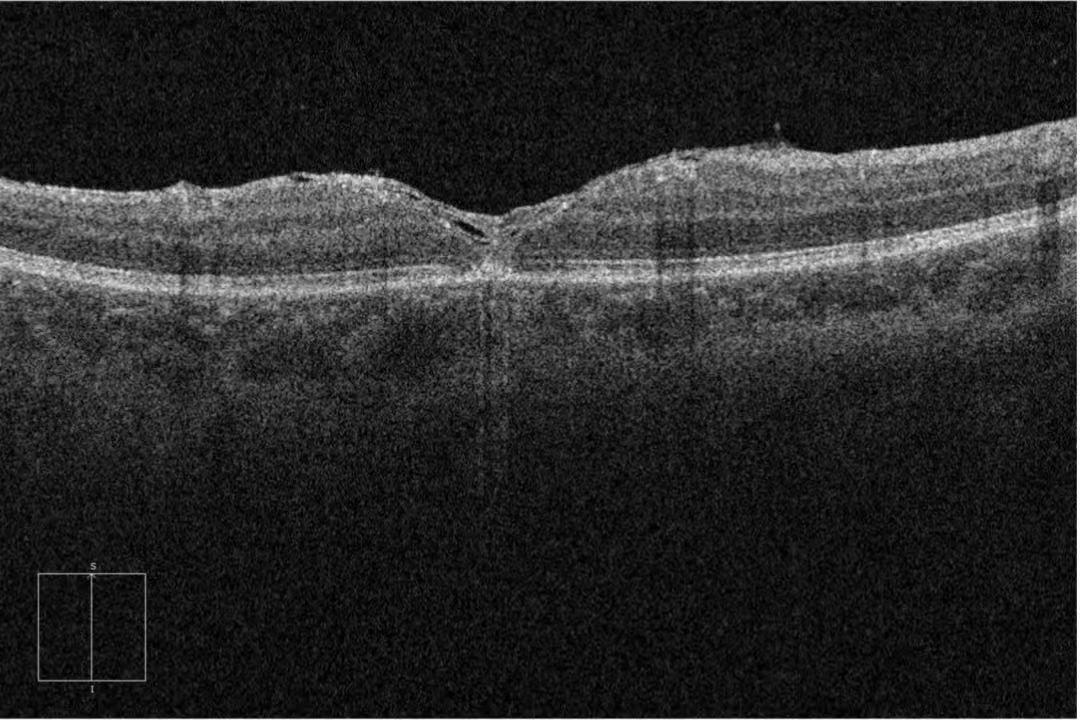

近一周,左眼视力下降加剧,严重影响吃饭、走路,洪女士才赶往广州市花都区人民医院眼科就诊。接诊医生结合症状高度怀疑黄斑病变,为其安排OCT(光学相干断层扫描)及欧堡超广角眼底检查,最终确诊为左眼全层黄斑裂孔并收治入院。

术后,眼科医护团队为洪女士定制个性化护理方案,密切监测眼压与视力,指导她做好体位管理和眼部防护。1个月后复查显示,视网膜平伏红润,黄斑裂孔完全闭合,神经上皮层贴合良好。拆纱布时,洪女士看着眼前清晰规整的世界,激动地说:“终于能看清了,看东西也不变形了,太感谢白主任和科室医护人员!”